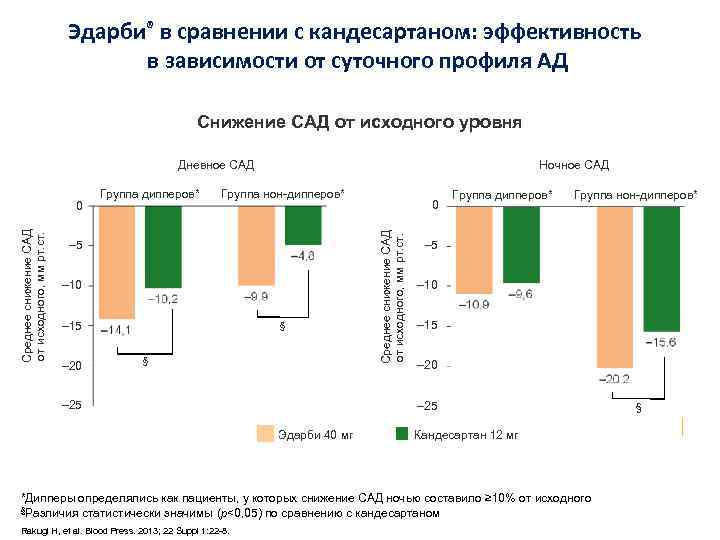

Эдарби® в сравнении с кандесартаном: эффективность в зависимости от суточного профиля АД Снижение САД от исходного уровня Дневное САД Группа дипперов* Группа нон-дипперов* – 5 – 10 – 15 – 20 § § – 25 0 Среднее снижение САД от исходного, мм рт. ст. 0 Ночное САД Группа дипперов* Группа нон-дипперов* – 5 – 10 – 15 – 20 – 25 Эдарби 40 мг Кандесартан 12 мг *Дипперы определялись как пациенты, у которых снижение САД ночью составило ≥ 10% от исходного §Различия статистически значимы (p<0, 05) по сравнению с кандесартаном Rakugi H, et al. Blood Press. 2013; 22 Suppl 1: 22 -8. §

Эдарби® в сравнении с кандесартаном: эффективность в зависимости от суточного профиля АД Снижение САД от исходного уровня Дневное САД Группа дипперов* Группа нон-дипперов* – 5 – 10 – 15 – 20 § § – 25 0 Среднее снижение САД от исходного, мм рт. ст. 0 Ночное САД Группа дипперов* Группа нон-дипперов* – 5 – 10 – 15 – 20 – 25 Эдарби 40 мг Кандесартан 12 мг *Дипперы определялись как пациенты, у которых снижение САД ночью составило ≥ 10% от исходного §Различия статистически значимы (p<0, 05) по сравнению с кандесартаном Rakugi H, et al. Blood Press. 2013; 22 Suppl 1: 22 -8. §